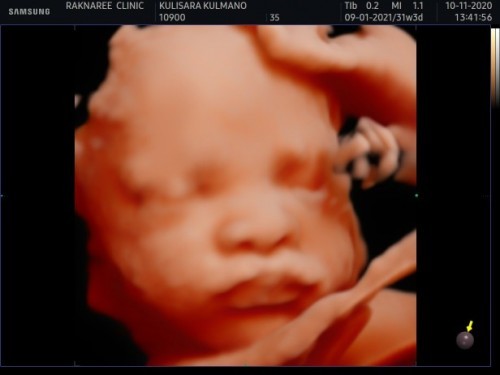

31 W 3 D

วันนี้ไปซาวด์ดูลูกสาวมา ลูกสาวให้ความร่วมมือดีมากคะ

ชัดเจนดีมากเลยค่ะ ไปซาวด์ที่เดียวกันเลยค่ะแม่ รักษ์นรีคลินิค บ้านนี้เอามือบังหน้า พยาบาลช่วยเขย่าแล้วเขย่าอีกค่ะ 555